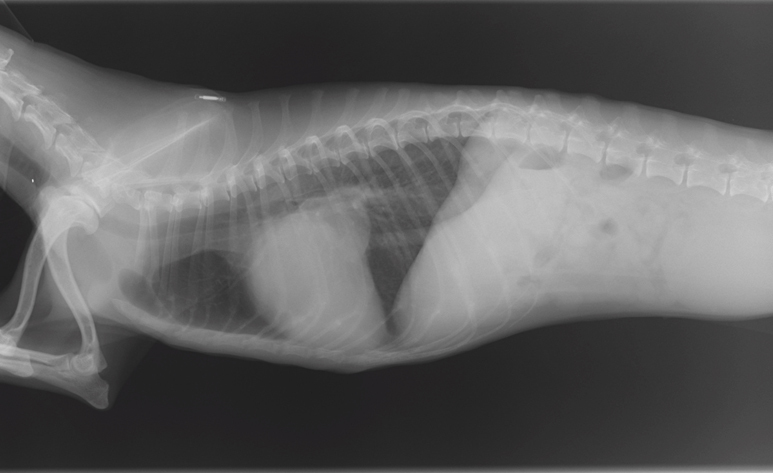

| 検査 | 身体検査、聴診、レントゲン検査、超音波検査、心電図検査、血圧測定、血液検査 |

症状や検査結果を基に、薬の種類や量を決めていきます。また、病状の進行によって種類、量が変わるので、定期的な検査をします。

心臓病の検査で特に大きな要となるのが、超音波検査でありますが、大変高い技術が求められる検査であります。この技術により診断が左右することも大いにあります。当院では幅広い知識と高い技術で検査を行い、診断しております。この検査では、動物に横になったり、仰向けになったりしてもらいますが、その姿勢が苦手な子、またその姿勢によって息苦しくなってしまう子に対しては、立ったままの姿勢での検査を行っております。